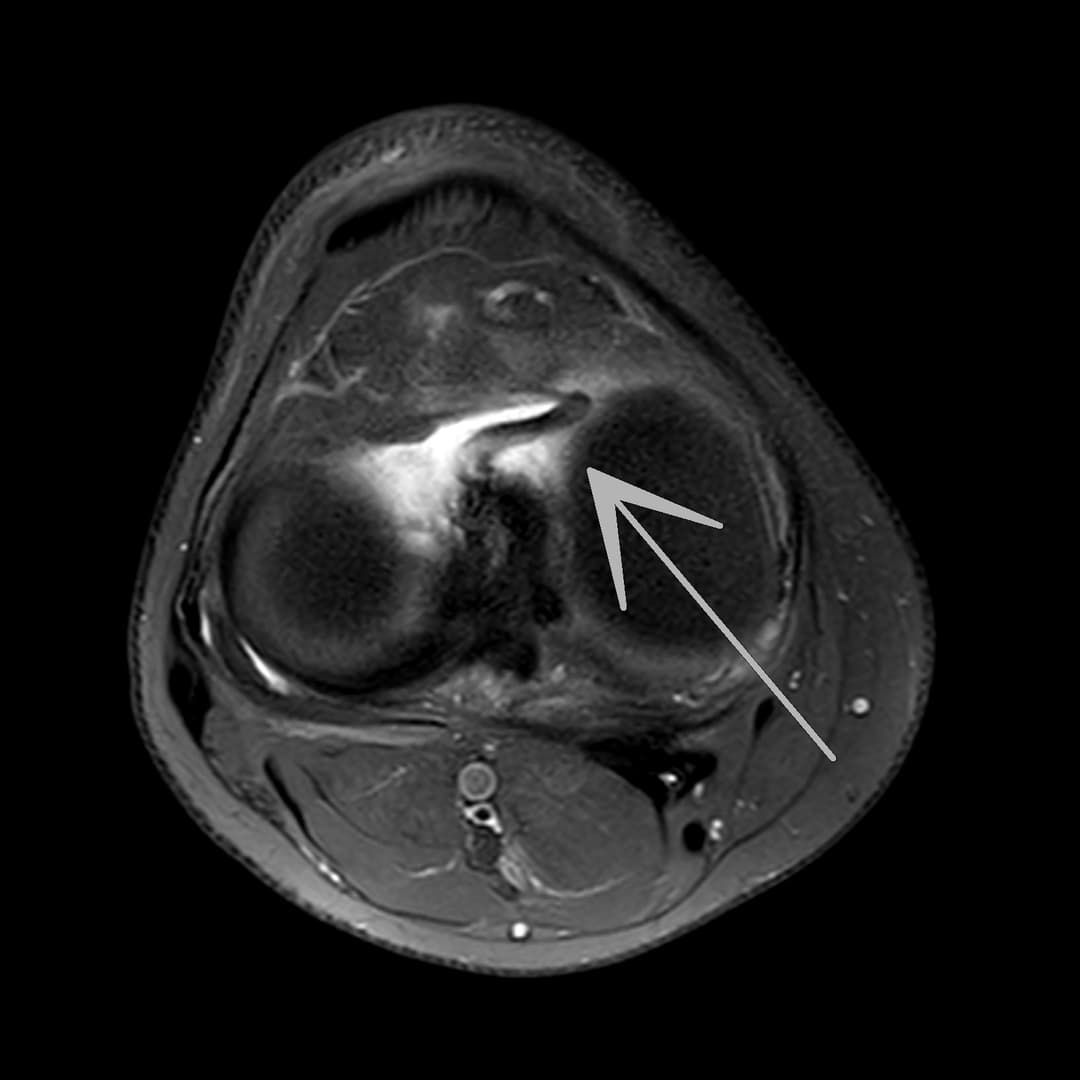

Languette méniscale rattachée à la corne antérieure du ménisque médial avec aspect flottant sur le versant antérieur de l'échancrure.